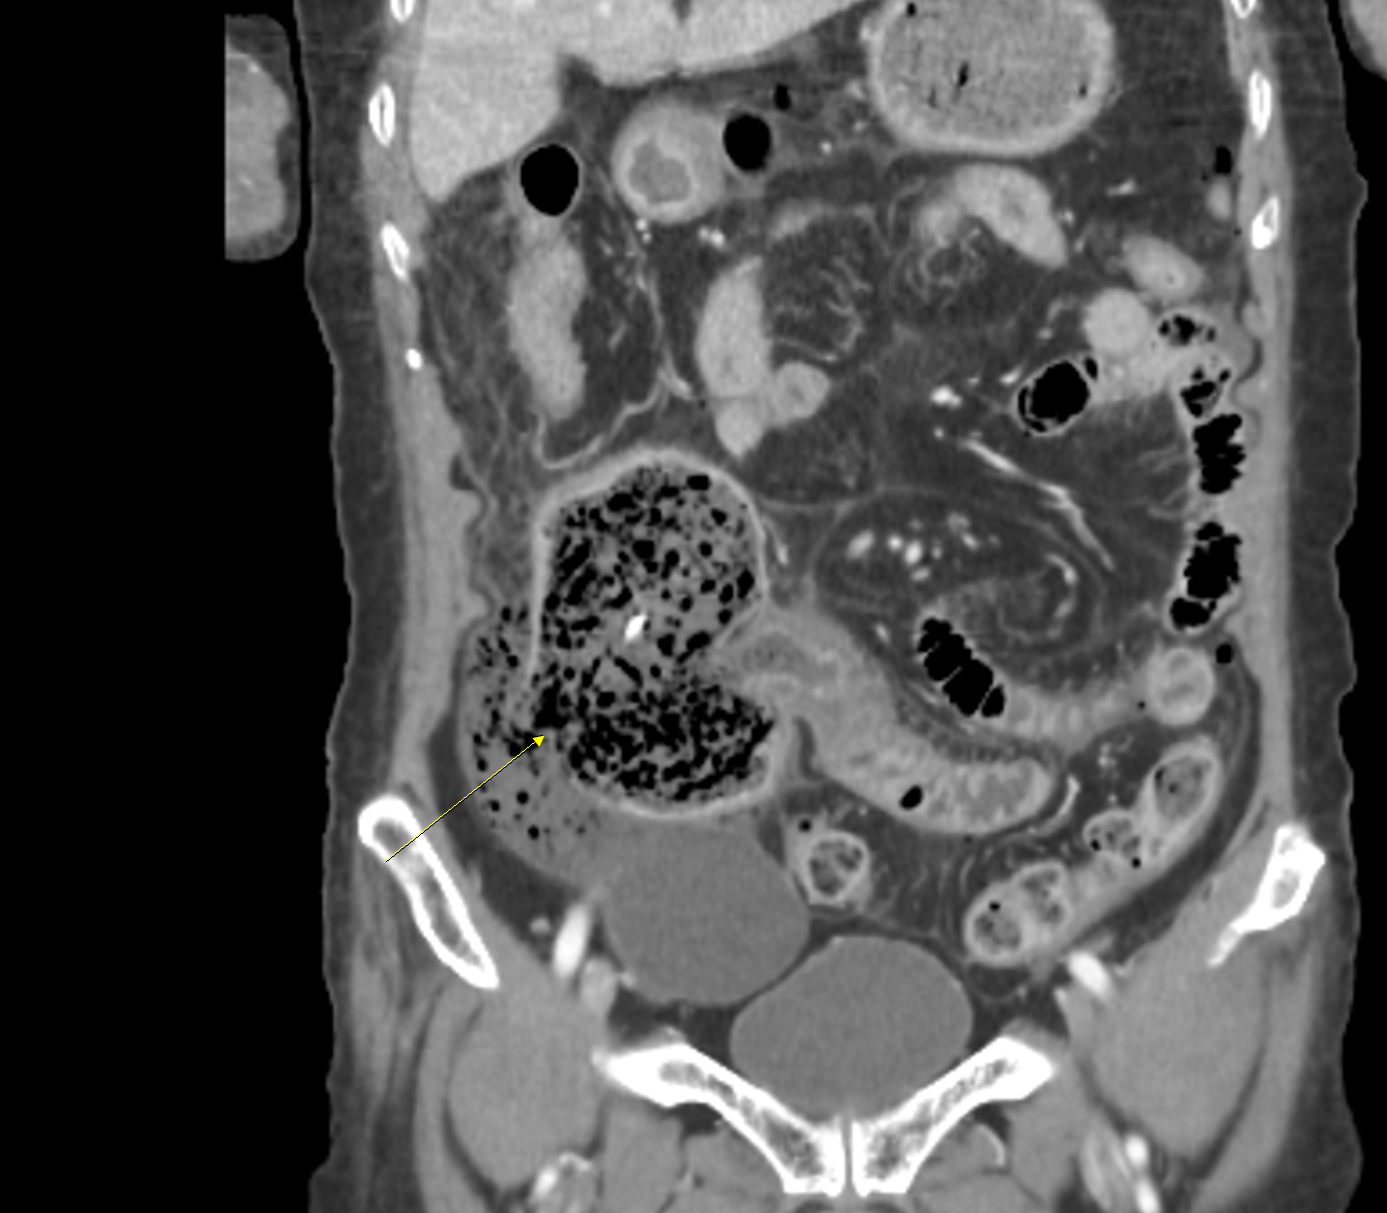

CT 검사 결과는 충격적이었다.

상행대장이 터지면서 복강 내로 대변이 잔뜩 흘러나와 있었고

장파열에 의한 복막염이 심한 상태였다.